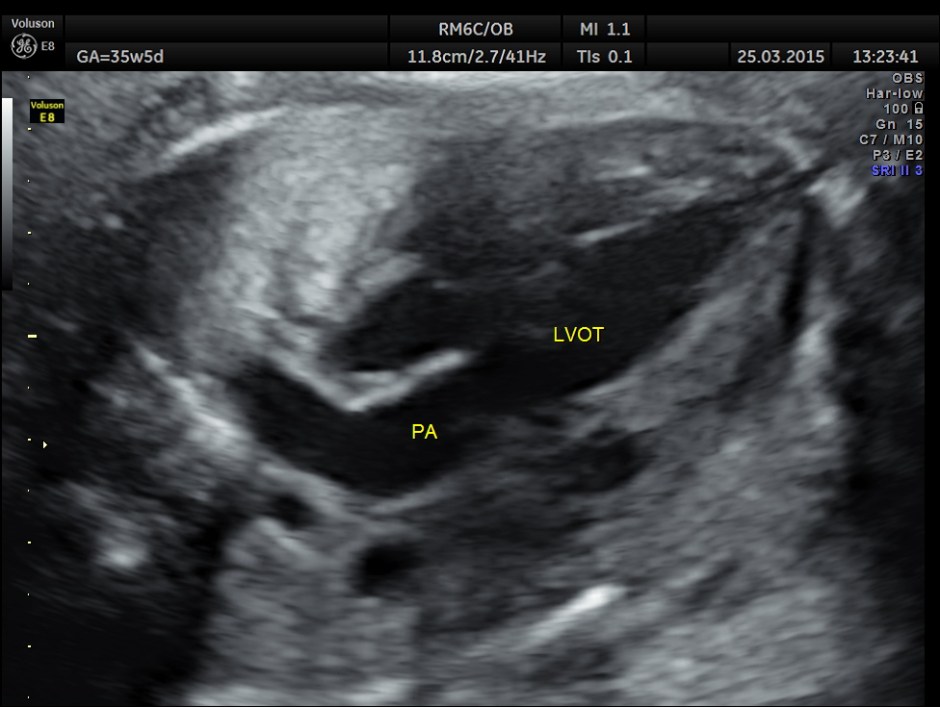

The great vessel arising from the right ventricle instead of crossing runs parallel to the vessel arising from the LV.

The great artery arising from the hypoplastic right ventricle runs parallel to the artery arising from the left ventricle.